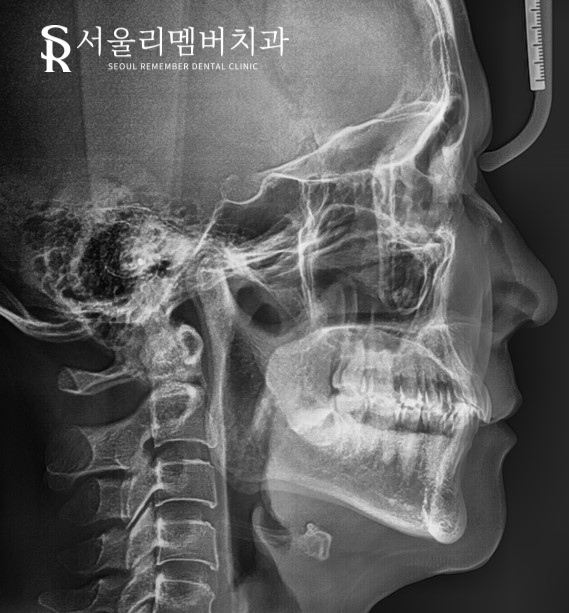

자, 우선 구강 내를 육안으로 확인했습니다.

다행히 골격 문제는 나타나지 않는 것으로 판단이 되었습니다.

아래턱이나 위턱이 발달된 경우는 나이 제한을 받을 수밖에 없습니다.

구강 내를 확인했습니다.

상악은 앞니의 뻐드러짐과

몇몇 치아들의 삐뚤어짐 빼고 별다른 문제가 나타나지 않았는데요.

하악 총생(crowding) 문제가 심했습니다.

들쑥날쑥 배열된 치아들은 물론이며 악궁의 형태가 바로 잡혀 있지 않았습니다.

특히 소구치를 보면 설측(혀)으로 치우쳐져 있는 모습이 관찰됩니다.

아예 오른쪽 앞니 하나는 있어야 될 자리에서 벗어나 바깥쪽으로 맹출 되어 있었습니다.

정면 사진을 살펴보면 정중선은 크게 삐뚤어지지 않았지만

윗니가 아랫니를 많이 덮는 과개교합(deep bite)이 나타나고 있었네요.